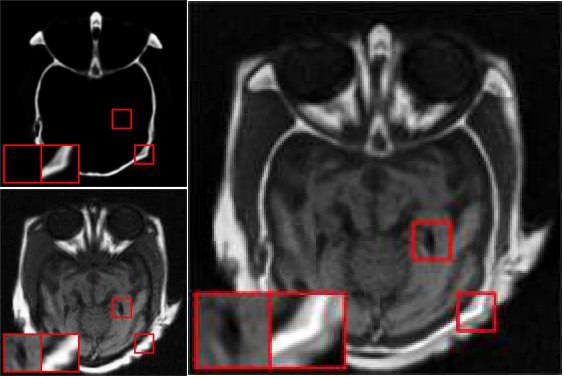

همجوشي دو يا چند تصوير

به منظور غناي اطلاعاتي تصوير (مثلاً ترکيب تصاوير معمولي با تراهرتز يا با تصاوير فروسرخ ).

به منظورهاي پزشکي و تعيين بيماري